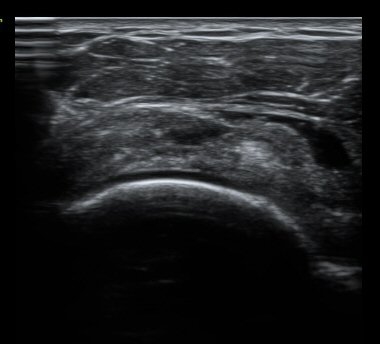

ȸÀü±Ù°³°£°Ý Ⱦ´Ü¸é°Ë»ç¿¡¼­ Á¡¾×³¶³» ¼ö¾×Àú·ù°¡ °üÂûµÈ´Ù(±×¸² 1). ÀÌµÎ¹Ú±Ù°Ç °í¶û¿¡¼­´Â ƯÀÌ ¼Ò°ßÀ» º¸ÀÌÁö ¾Ê´Â´Ù(±×¸² 2). ȸÀü±Ù°³°£°Ý ³»Ãø¿¡¼­ °ß°©ÇϱٰÇÀÇ ÆÄ¿­°ú Á¡¾×³¶³» ¼ö¾×Àú·ù°¡ °üÂûµÈ´Ù(±×¸² 3, 4). ±Ø»ó°Ç Ⱦ´Ü